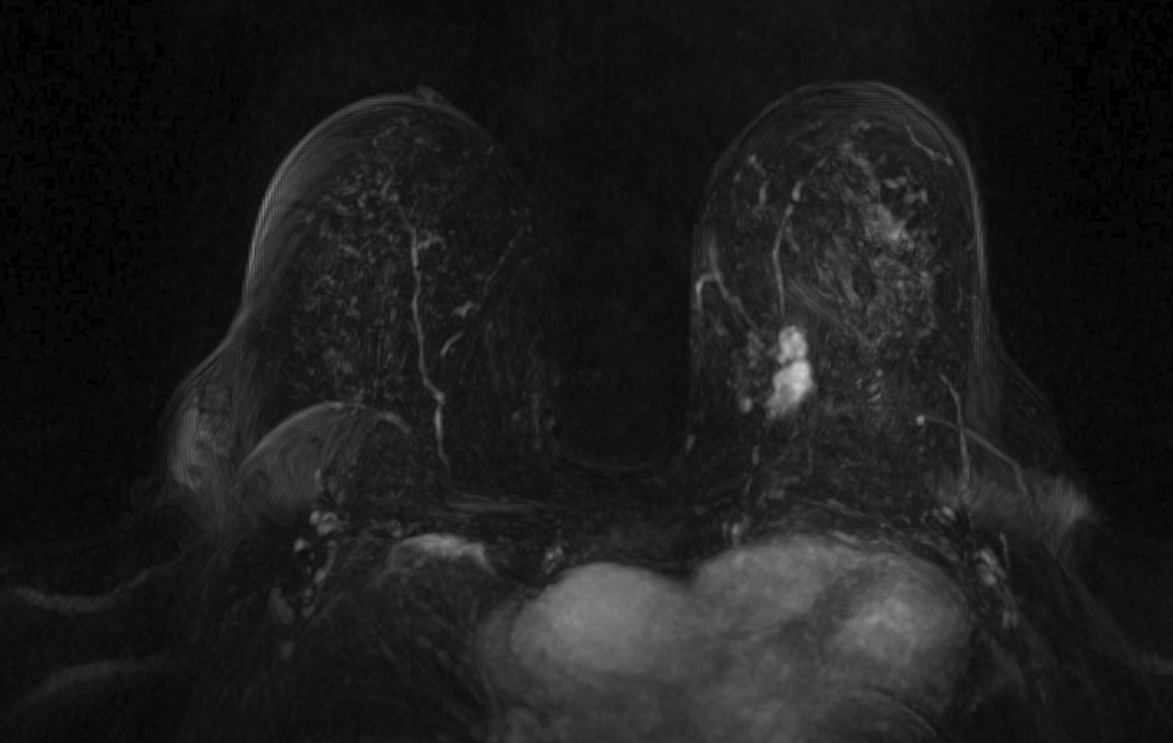

Magnetic resonance imaging (MRI) has been used as an adjunctive screening tool, mainly for women who may be at increased risk for the development of breast cancer. Example images of MRI are shown in fig. 5 with T1 contrast enhancement. MRI for screening has not been very popular in women with average risk due to concerns about the low specificity leading to additional biopsies, time and cost of technology [26]. Breast MRI sensitivity values reported in high risk screening studies range from 93% to 99%. Despite its high sensitivity, breast MRI has been reported to have variable specificity, ranging from 50% to 85% [27]. These number of sensitivity and specificity depends on the type of tumor, size of tumor, age of patient, and where it is localised.